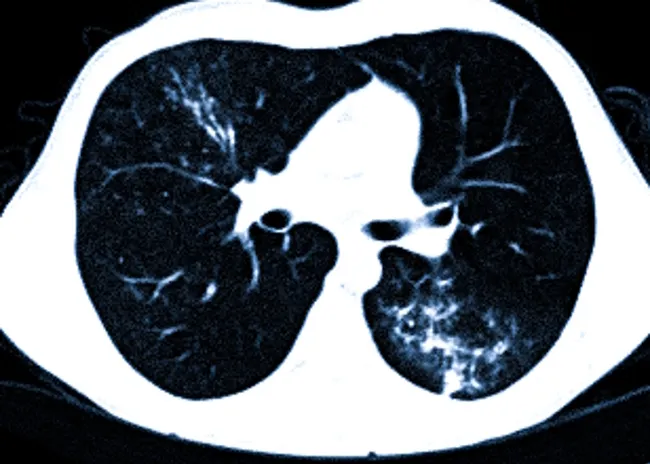

Динамическое наблюдение с помощью КТ особенно важно при лечении онкологических заболеваний, где необходимо отслеживать реакцию опухоли на химиотерапию, лучевую терапию или таргетную терапию․ Однако, применение КТ не ограничивается онкологией․ В других областях медицины, таких как травматология, нейрохирургия и пульмонология, КТ также незаменима для оценки эффективности лечения и контроля за динамикой патологического процесса․

В других областях медицины параметры оценки эффективности лечения на КТ могут быть различными․ Например, при травмах костей оценивают степень сращения переломов, при заболеваниях легких – динамику воспалительного процесса, при заболеваниях головного мозга – размеры гематом или отеков․

| Заболевания легких | Динамика воспалительного процесса, наличие инфильтратов |